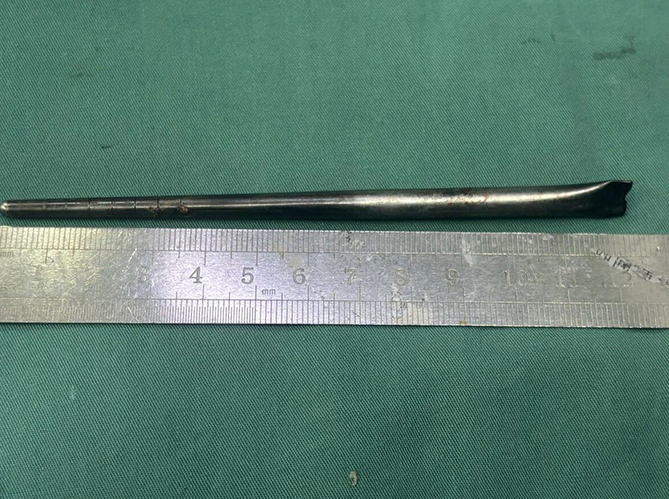

Dalian Belediye Merkez Hastanesi’ne boğazında şiddetli ağrı ve yabancı cisim hissi şikayetiyle giden Bay Wang’ın yapılan röntgen muayenesinde, boğaz bölgesine saplanmış metal bir mil tespit edildi. Hastanın, doktorların sorusu üzerine durumu onaylayarak sekiz yıl önce yemek yerken yanlışlıkla bir metal yemek çubuğu yuttuğunu ifade ettiği bildirildi.

TEK PARÇA HALİNDE ÇIKARILDI

Dalian Teknoloji Üniversitesi Bağlı Merkez Hastanesi Kulak Burun Boğaz Bölümü uzmanları, hayati damarlara ve mukoza dokusuna zarar verme riski bulunan cisim için minimal invaziv (kapalı cerrahi) yöntemini tercih etti. Dr. Huang Weipeng ve ekibi tarafından gerçekleştirilen operasyonla, 12 santimetre uzunluğundaki paslanmaz çelik çubuk dokulardan ayrılarak tek parça halinde çıkarıldı.